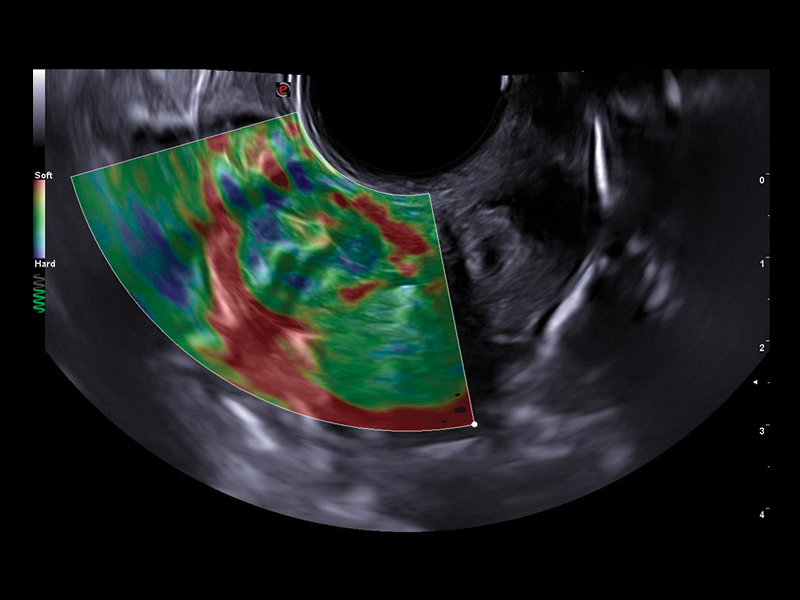

By associating various chromatic patterns, Esaote’s ElaXto strain technology offers real-time assessment of differing tissue response in terms of elasticity, to evaluate cervix elasticity for a proper embryo transfer.